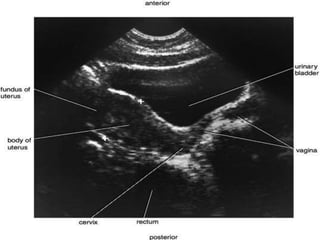

The urinary bladder develops during the 18th week of fetal development. It is located in the pelvic cavity behind the pubic symphysis in males and anterior to the uterus in females. The bladder has a muscular wall and receives its blood supply from branches of the internal iliac artery, including the superior and inferior vesical arteries. Nerve supply comes from pelvic splanchnic nerves via the hypogastric plexus and pudendal nerves. The bladder drains lymph into pelvic lymph nodes and is supported by ligaments attached to surrounding structures in the pelvis. Microscopically, it has a mucosa, submucosa, muscularis and adventitia layers.